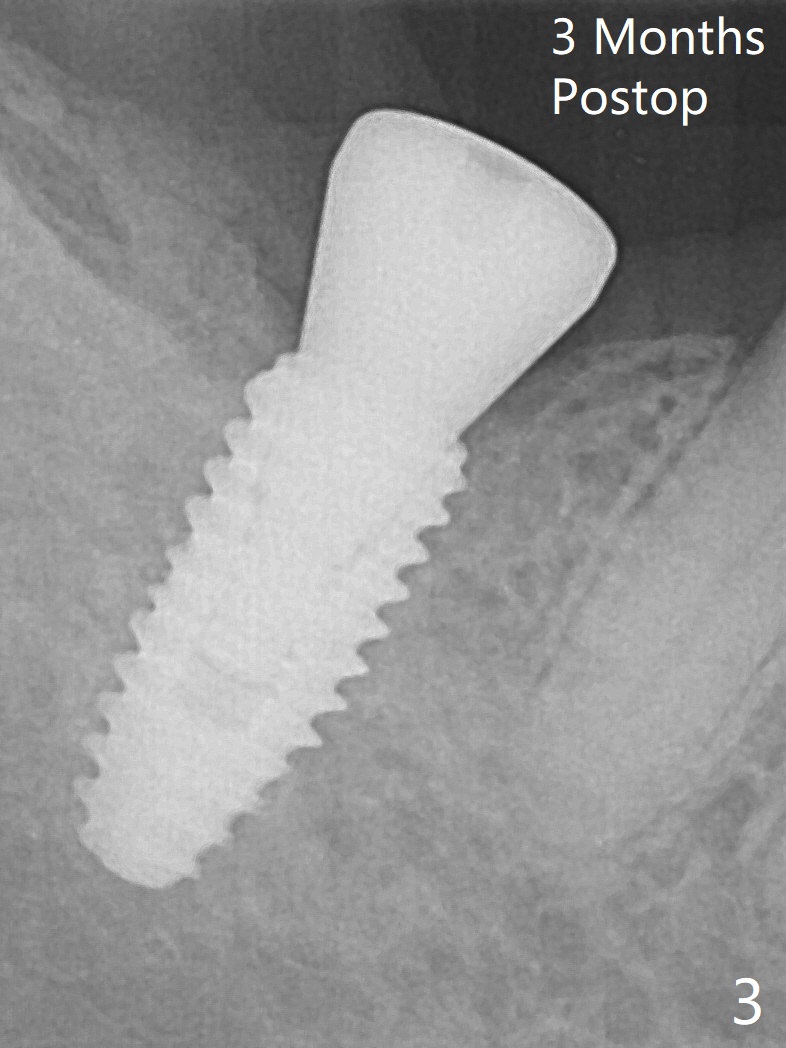

After placement of a 4.5x10 mm implant with guide at #31 and before placement of a 6x4 (Fig.1) and finally a 5.5x4 (Fig.2) mm healing abutment, a 5.7x5(2) mm dummy (planning) abutment is placed without restorative space. It appears that either orthodontic or restorative intrusion is necessary. The patient prefers the latter. The reasons of switching the large healing abutment to the smaller one are two-folded. The primary stability of the implant is ~ 10 Ncm. Tongue mobility may cause fibrointegration. The 6 mm abutment seems to contact the mesial crestal bone (Fig.1). In fact the smaller abutment does not help much. It may be related to radiation angulation. A smaller sensor will be used to reduce the angulation 3-4 months later. In fact #1 sensor does produce better image with less angulation (Fig.3). After trimming a 5.2x4.5(3) mm abutment and opposing tooth (palatal cusp), impression is taken.